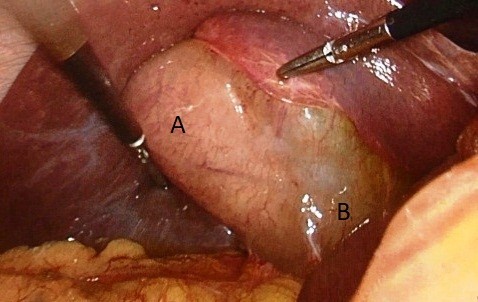

Se realizó colecistectomía laparoscópica. Del intraoperatorio destacamos, doble cuerpo vesicular, envueltos por un mismo peritoneo visceral, uno con colecistitis, el otro sin signos inflamatorios (ver imagen 3).

Imagen 3: Duplicación vesicular. A: cuerpo vesicular con colecistitis. B: cuerpo vesicular sin colecistitis.